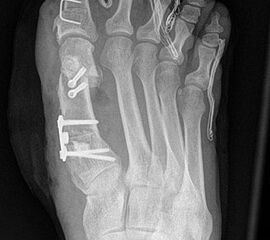

Die dorsoplantaren Röntgenaufnahmen zeigen eine Open-wedge Technik mit der normalerweise ein erhöhter intermetatarsaler Winkel gut zu korrigieren ist (Abbildung 3). Die Wirksamkeit einer Basisosteotomie ist umso größer, je proximaler diese durchgeführt wird. Je weiter distal die Osteotomie, umso geringer die Korrektur. Auf den postoperativen Bildern ist der distal unverändert große Abstand zwischen Metatarsale I und Metatarsale II erkennbar, bei gleichzeitiger Subluxation des Großzehengrundgelenks und dezentrierten Sesambeinen. Darüber hinaus finden sich initiale degenerative Veränderungen im Großzehengrundgelenk. Klinisch bestand eine hohe Weichteilspannung, bei verkürzter Extensor- und Flexor hallucis longus Sehne.  Daher wurde ein verkürzendes Verfahren zur Revision gewählt (Abbildung 4). Die Lapidusarthrodese stellt ein sehr zuverlässiges Verfahren zur Behandlung von Hallux valgus Rezidiven dar 9. Die Fusion des Tarsometatarsale-I-Gelenks kombiniert Stabilität mit einem hohen Korrekturpotenzial. Aufgrund der verfahrensimmanenten Verkürzung des ersten Strahls und der in diesem Fall bereits präoperativ vorhandenen Transfermetatarsalgie wurde die Entscheidung für eine verkürzte Weil-Osteotomie am zweiten bis fünften Strahl gefällt. Die Kombination beider Verfahren führte zu einem homogenen Metatarsale-Index und zu einer gleichmäßigen plantaren Druckverteilung 10. Die Hallux valgus interphalangeus Fehlstellung wurde mit einer Akin-Osteotomie korrigiert.